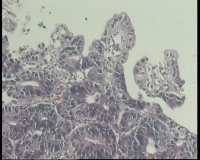

请教,胃溃疡,癌变吗?

胃窦溃疡性病变

胃窦变形,粘膜变薄,粘膜下血管网透见,前壁见不规则溃疡1.6x1.4lm ,周围粘膜呈不规则隆起

活检组织4块。请老师看看高级别癌变吗?倒数第4图纤维间质内腺体,是浸润吗?

可以报癌了。

腺癌。

腺癌,黏膜肌层浸润。